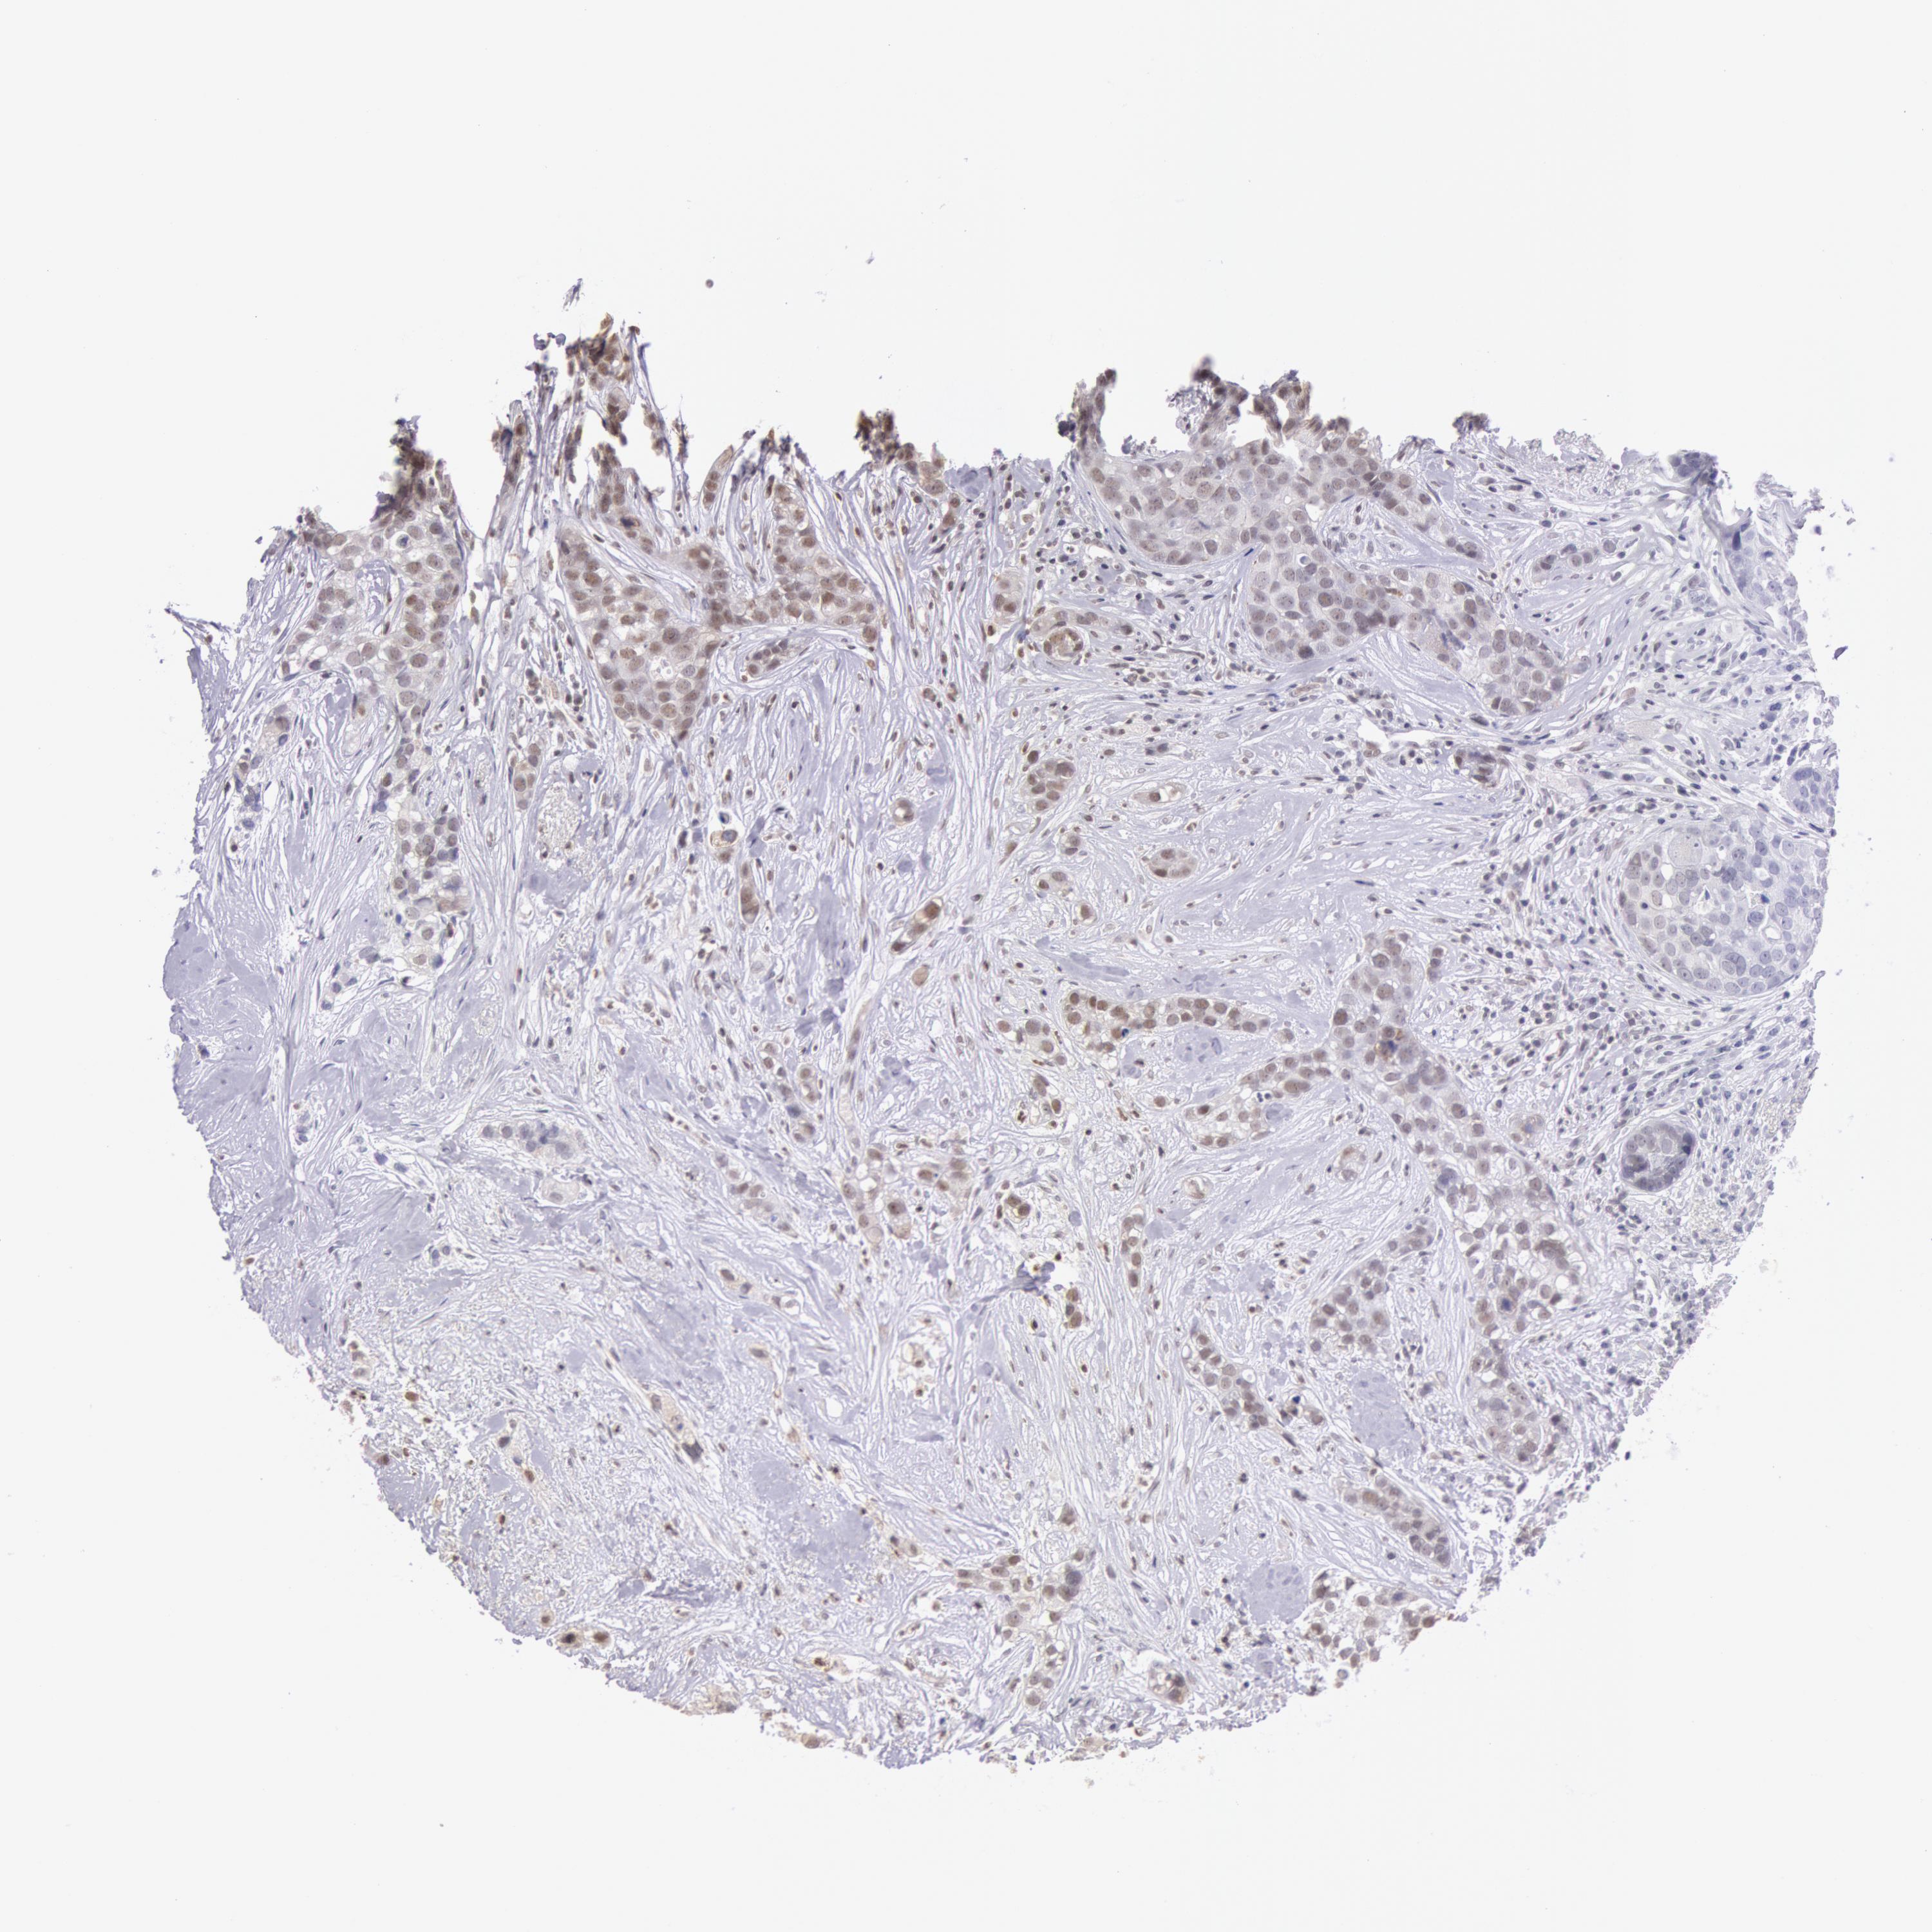

BRCA TCGA BRCA VALIDATION PROTEIN EXPRESSION